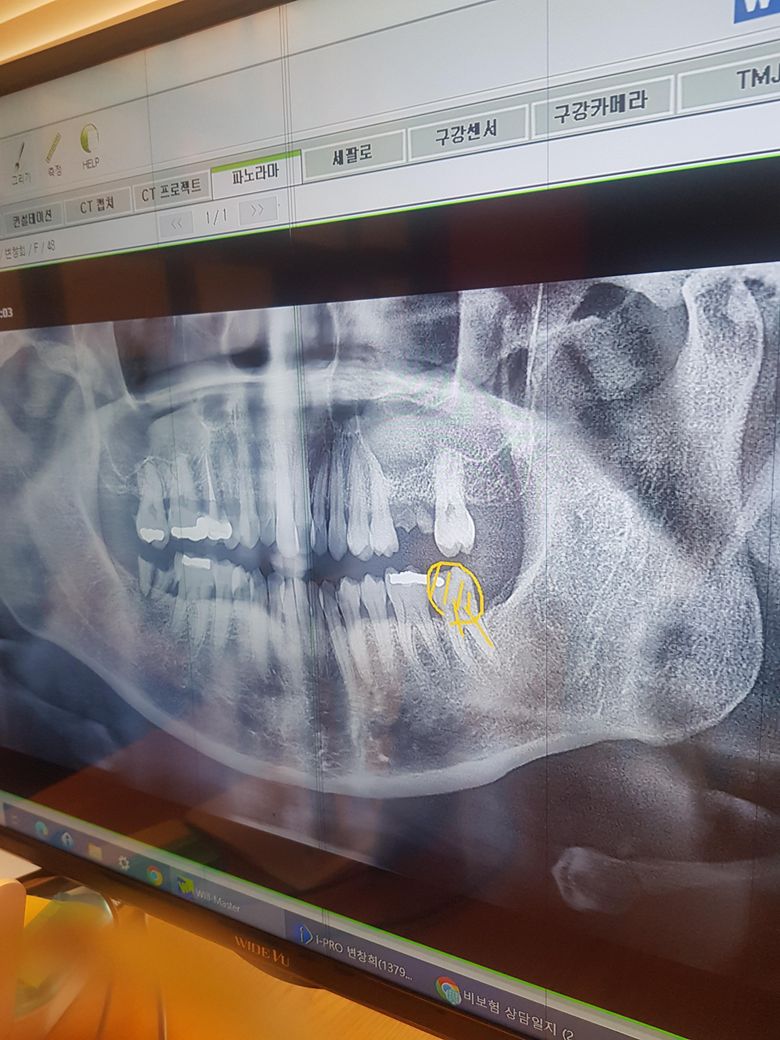

치과치료심비용과 충치문의드립니다.

첫신경치료후 수납할때 심비용 10만원 내라고해서 친구카드빌려서급히 냈는데 제지인이 심비용은 신경치료다하고 내는거라고 과잉 진료하는곳 아닌지 물어보래요. 신경치료비13만원나온다고햇는데 의료헤택받아서 안내도된다고하면서 첫날에 심비용 냈는데 중간에 병원바꿀까바 먼저 받은건가요? 몰라서 여쭈어봅니다. ㅠ그리고 충치가깊다고하는데 충치가안보이는데 어디보고 깊다고하는걸까요? ㅠ 감사합니다

충치는 보입니다.

3. 기존 보철물이 파절되어 신경치료가 불가피하다고 판단한 것 같습니다.